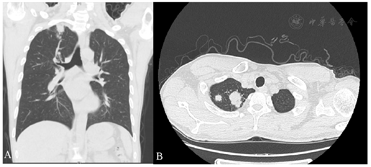

入院行血常规提示白细胞14.03×109/L、红细胞3.85×1012/L、血红蛋白111g/L、淋巴细胞百分数4%、中性粒细胞百分数89.4%,余无明显异常。鼻窦CT及MRI检查提示左侧鼻腔、上颌窦、额窦及双侧筛窦、蝶窦、鼻咽部软组织病变,不均匀强化,伴下鼻甲骨质破坏(图2)。

肺部CT见双肺上叶、右肺中叶多发散在结节状高密度影,边缘欠规则,密度均匀,大者位于右肺尖,大小约31mm×26mm,周围散在多发索条影及小结影,并见索条影牵拉胸膜。左下肺胸膜下小结节高密度影,边界清,气管及主支气管通畅,肺门、纵膈未见肿大淋巴结,胸腔内未见积液征。不除外真菌感染或结核(图3)。